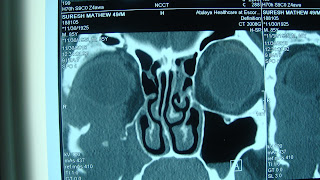

The case was operated upon by right infraorbital incision, right sublabial incision and right FESS to marsupialize the cyst which drained into right nose. the patient is doing fine in postoperative period with slight diplopia in certain eye movements.